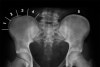

특발성 측만증의 영상 검사

- PA, Lateral view including Iliac crest, C-spine

기립 촬영이 원칙 / Cobb’s angle 측정

5도 이상의 변화가 있을때 의미 있는 변화

* Risser sign

Grade 0 : The apophysis is still visible

Grade I : The apophysis starts to develop in the anterior area of the iliac crest (beginning ossification) Grade II : The apophysis covers half the iliac crest

Grade III : The apophysis now covers three quarters of the iliac crest

Grade IV : The apophysis of the iliac crest completely covers the iliac crest. The fusion starts in the posterior segment.

Grade V : The iliac bone is completely fused to the apophysis of the iliac crest.